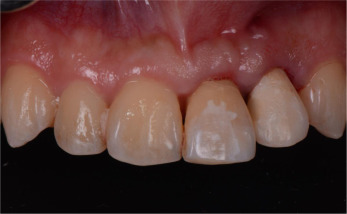

A twenty-six year old male patient was referred for the management of the symptomatic maxillary left central and lateral incisors. The incisors were diagnosed with external root resorption due to history of trauma. The long-term endodontic prognoses were assessed to be poor (Figs. 1 a, b and 2 ).

(a) Labial view of the pre-operative clinical condition. (b) Palatal view of the pre-operative clinical condition.